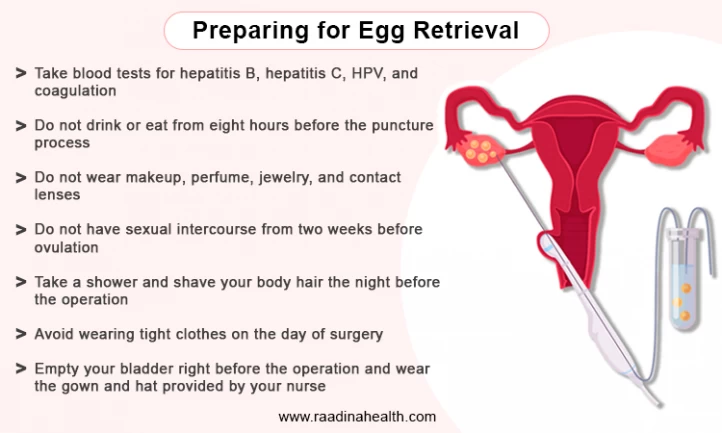

Step 4: The Big Day—Egg Retrieval

What Happens?

Now it’s showtime! Egg retrieval is a quick procedure (about 10-20 minutes) done under sedation. Here’s the play-by-play:

- You’re hooked up to an IV with sleepy meds—think twilight nap, not full-on surgery vibes.

- The doctor uses an ultrasound wand (yep, back in the vagina) to spot your follicles.

- A thin needle goes through the vaginal wall into each follicle, sucking out the fluid—and the eggs—with a tiny vacuum.

- The eggs get whisked off to the lab while you snooze.

Practical Tips

✔️ Bring a cozy blanket or socks—operating rooms are chilly!

✔️ Arrange a ride home; you’ll be too groggy to drive.

❌ Don’t wear perfume or makeup—keeps the sterile vibe intact.